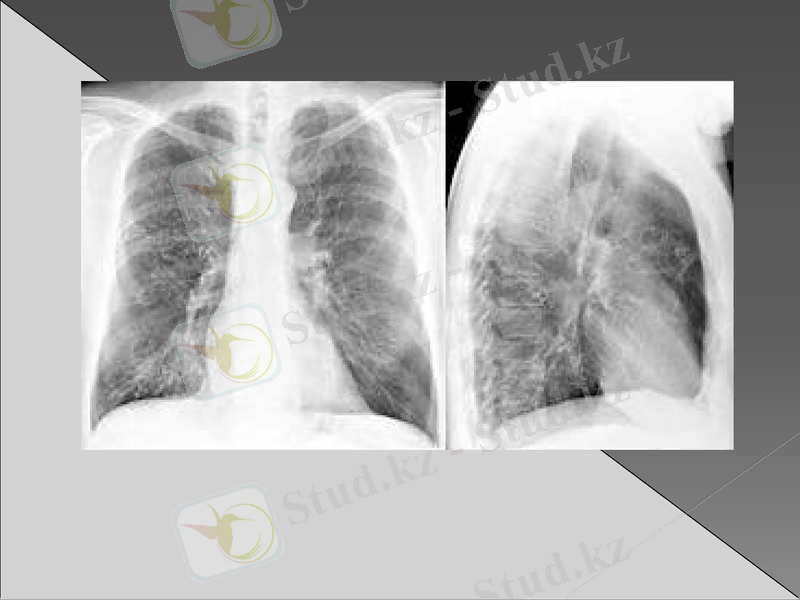

2. Екі жақты пневмония (көлемін көрсету керек) .

Рентгенография : инфильтрация немесе қараю зоналары (пневмонияның түріне байланысты өкпе тінінің зақымдалуы)

Рентгендік зерттеуде бірінші күні айқын көрінетін инфильтрациялық өзгерістер болмайды. Бұл кезде әрең байқалатын вуаль тәрізді нәзік көлеңкелену болуы мүмкін. Оның интенсивтілі біртіндеп күшейіп нағыз шыңына 5- тәулікте жетеді. Қан анализінде лейкоцитоз 15-30х 10/л дейін көбейеді. Лейко формулада нейтрофилдердің жетілмеген жас түрі көбейеді. ЭТЖ жоғарылайды. Сонымен бірге қанда қабынудың биохимиялық белгілері анықталады. Альфа және гамма глобулиндердің, фибриногеннің жоғарылауы, С реактивті белоктің пайда болуы. Қақырықта белоктің, фибриннің, эритроциттердің, лейкоциттердің мөлшері көп. Қақырық жағындысында қоздырғыш табылады.